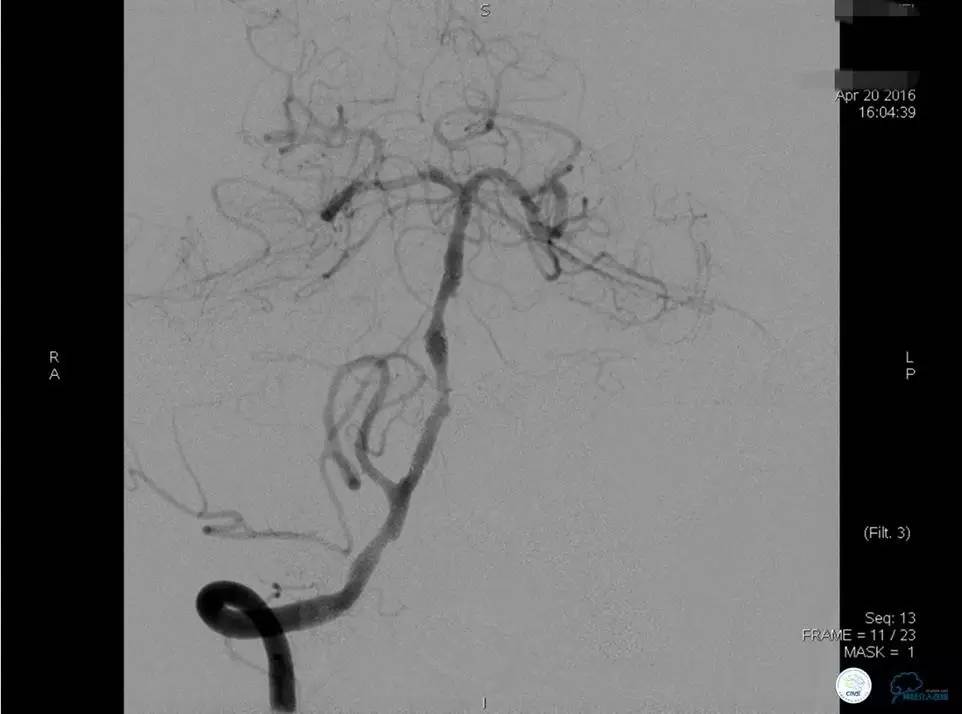

▼DSA示右侧椎动脉发育低下,弥漫性狭窄,可以看到左侧椎动脉反流,因此判断左侧椎动脉V4段CTO。

治疗:

微导丝穿过闭塞段,微导管造影,球扩闭塞段,置入Wingspan支架,血流完全恢复正常。